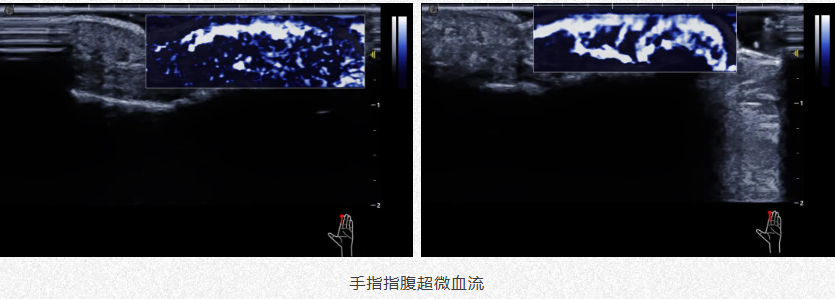

肌骨系统炎症监测

1.前期显示患处血供情况助力医生诊断。

2.中期精准定位避开血管防药物中毒。

3.后期评估疗效随访监测。

e6adc1f0e73b5c53c3f435a62f56c7a.png